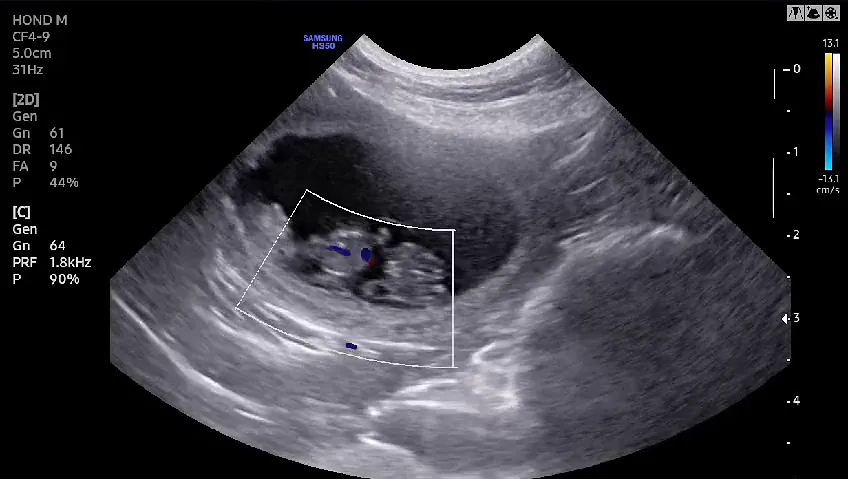

Dracht Echo

"Is uw dier drachtig? Met een drachtecho kunnen we op een veilige en pijnloze manier vaststellen of er kleintjes op komst zijn. Dit onderzoek biedt een eerste blik op de groei en ontwikkeling van het jonge leven. Bovendien helpt het ons om eventuele bijzonderheden tijdig op te sporen. Wilt u meer weten over hoe een drachtecho werkt? Klik dan op 'Meer lezen' voor uitgebreide informatie."

De Samsung HS50

Met trots laten we ons echoapparaat zien van dierenkliniek Schinnen: de Samsung HS50. Een modern krachtig apparaat met een aparte kop voor de hartecho en een voor de buikecho.

Wij streven we ernaar om uw huisdier de beste zorg te bieden. Daarom zijn we trots op onze investering in de Samsung HS50, een geavanceerd echografieapparaat dat ons helpt om nog nauwkeuriger en sneller diagnoses te stellen.

Met de HS50 kunnen we beelden van uitzonderlijke kwaliteit maken, waardoor we weefsels, organen en eventuele afwijkingen haarscherp in beeld brengen. Dit betekent dat we uw huisdier met meer precisie kunnen behandelen en samen met u de beste beslissingen kunnen nemen over hun gezondheid.